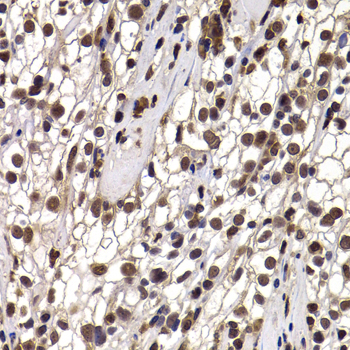

• A7034: image 3

Immunohistochemistry of paraffin-embedded human kidney cancer using DDX21 antibody at dilution of 1:100 (40x lens).